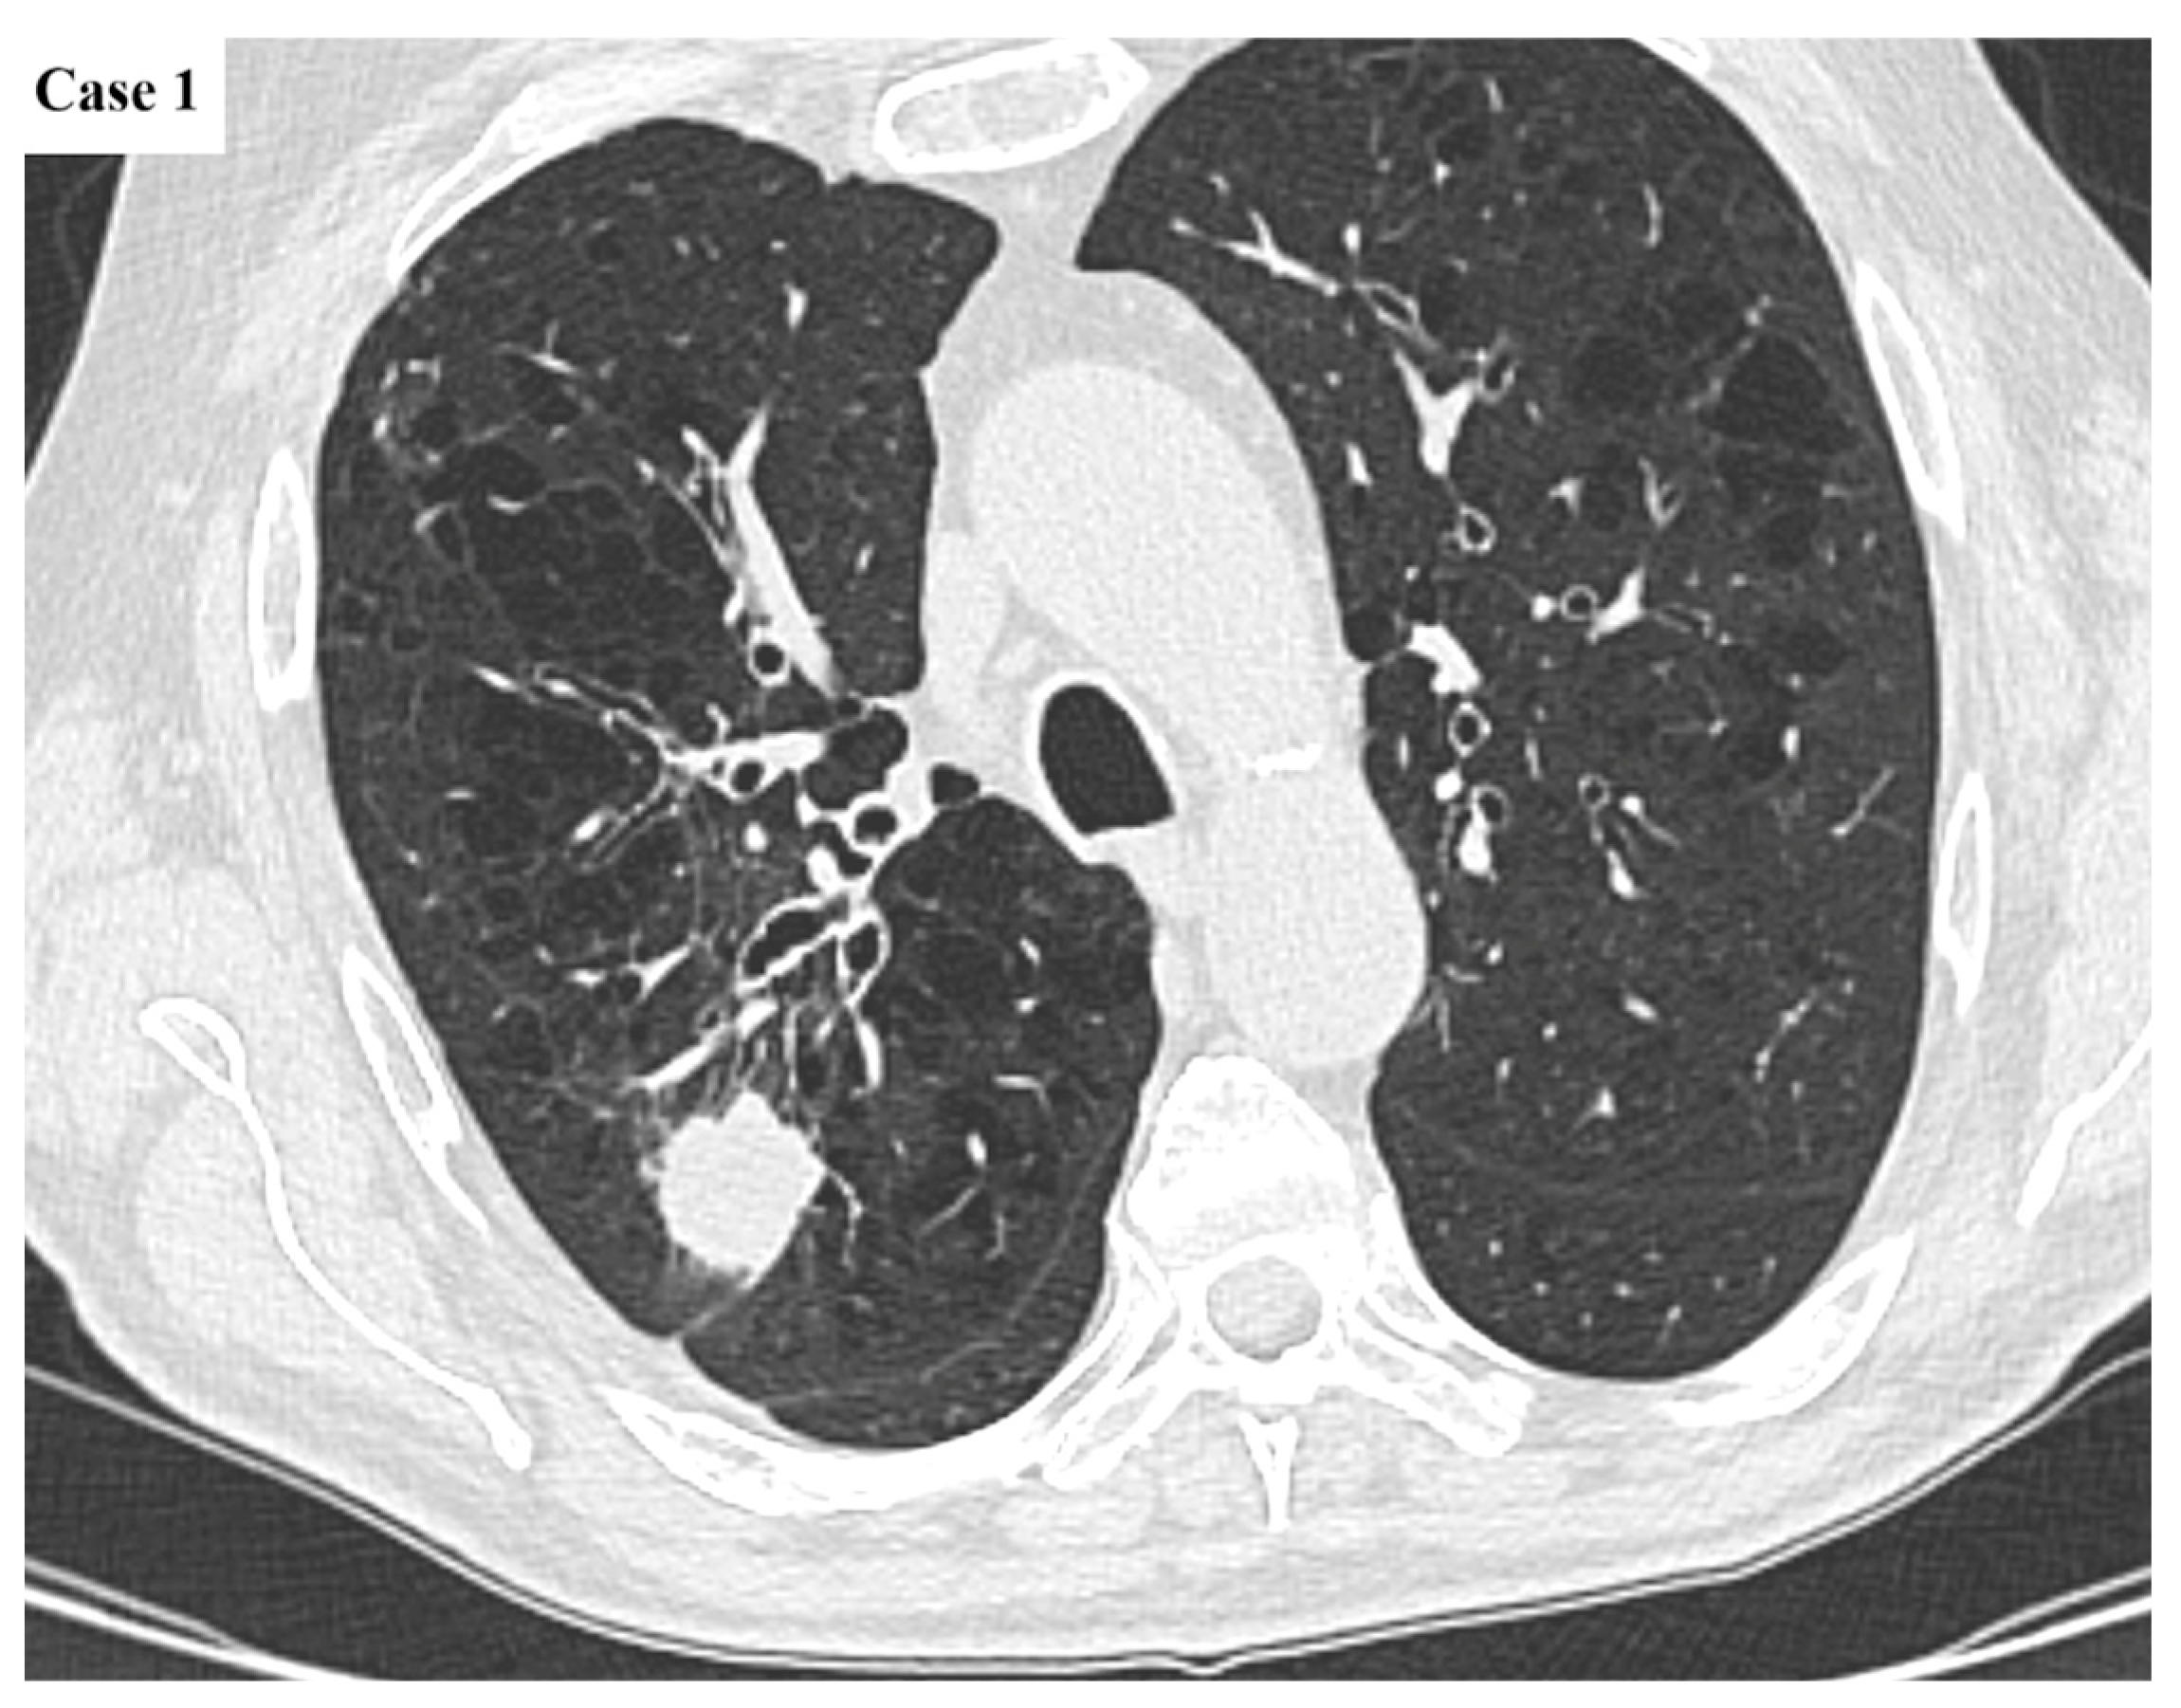

2.2. Data Collection and Imaging Evaluation

2.3. Staging Procedures